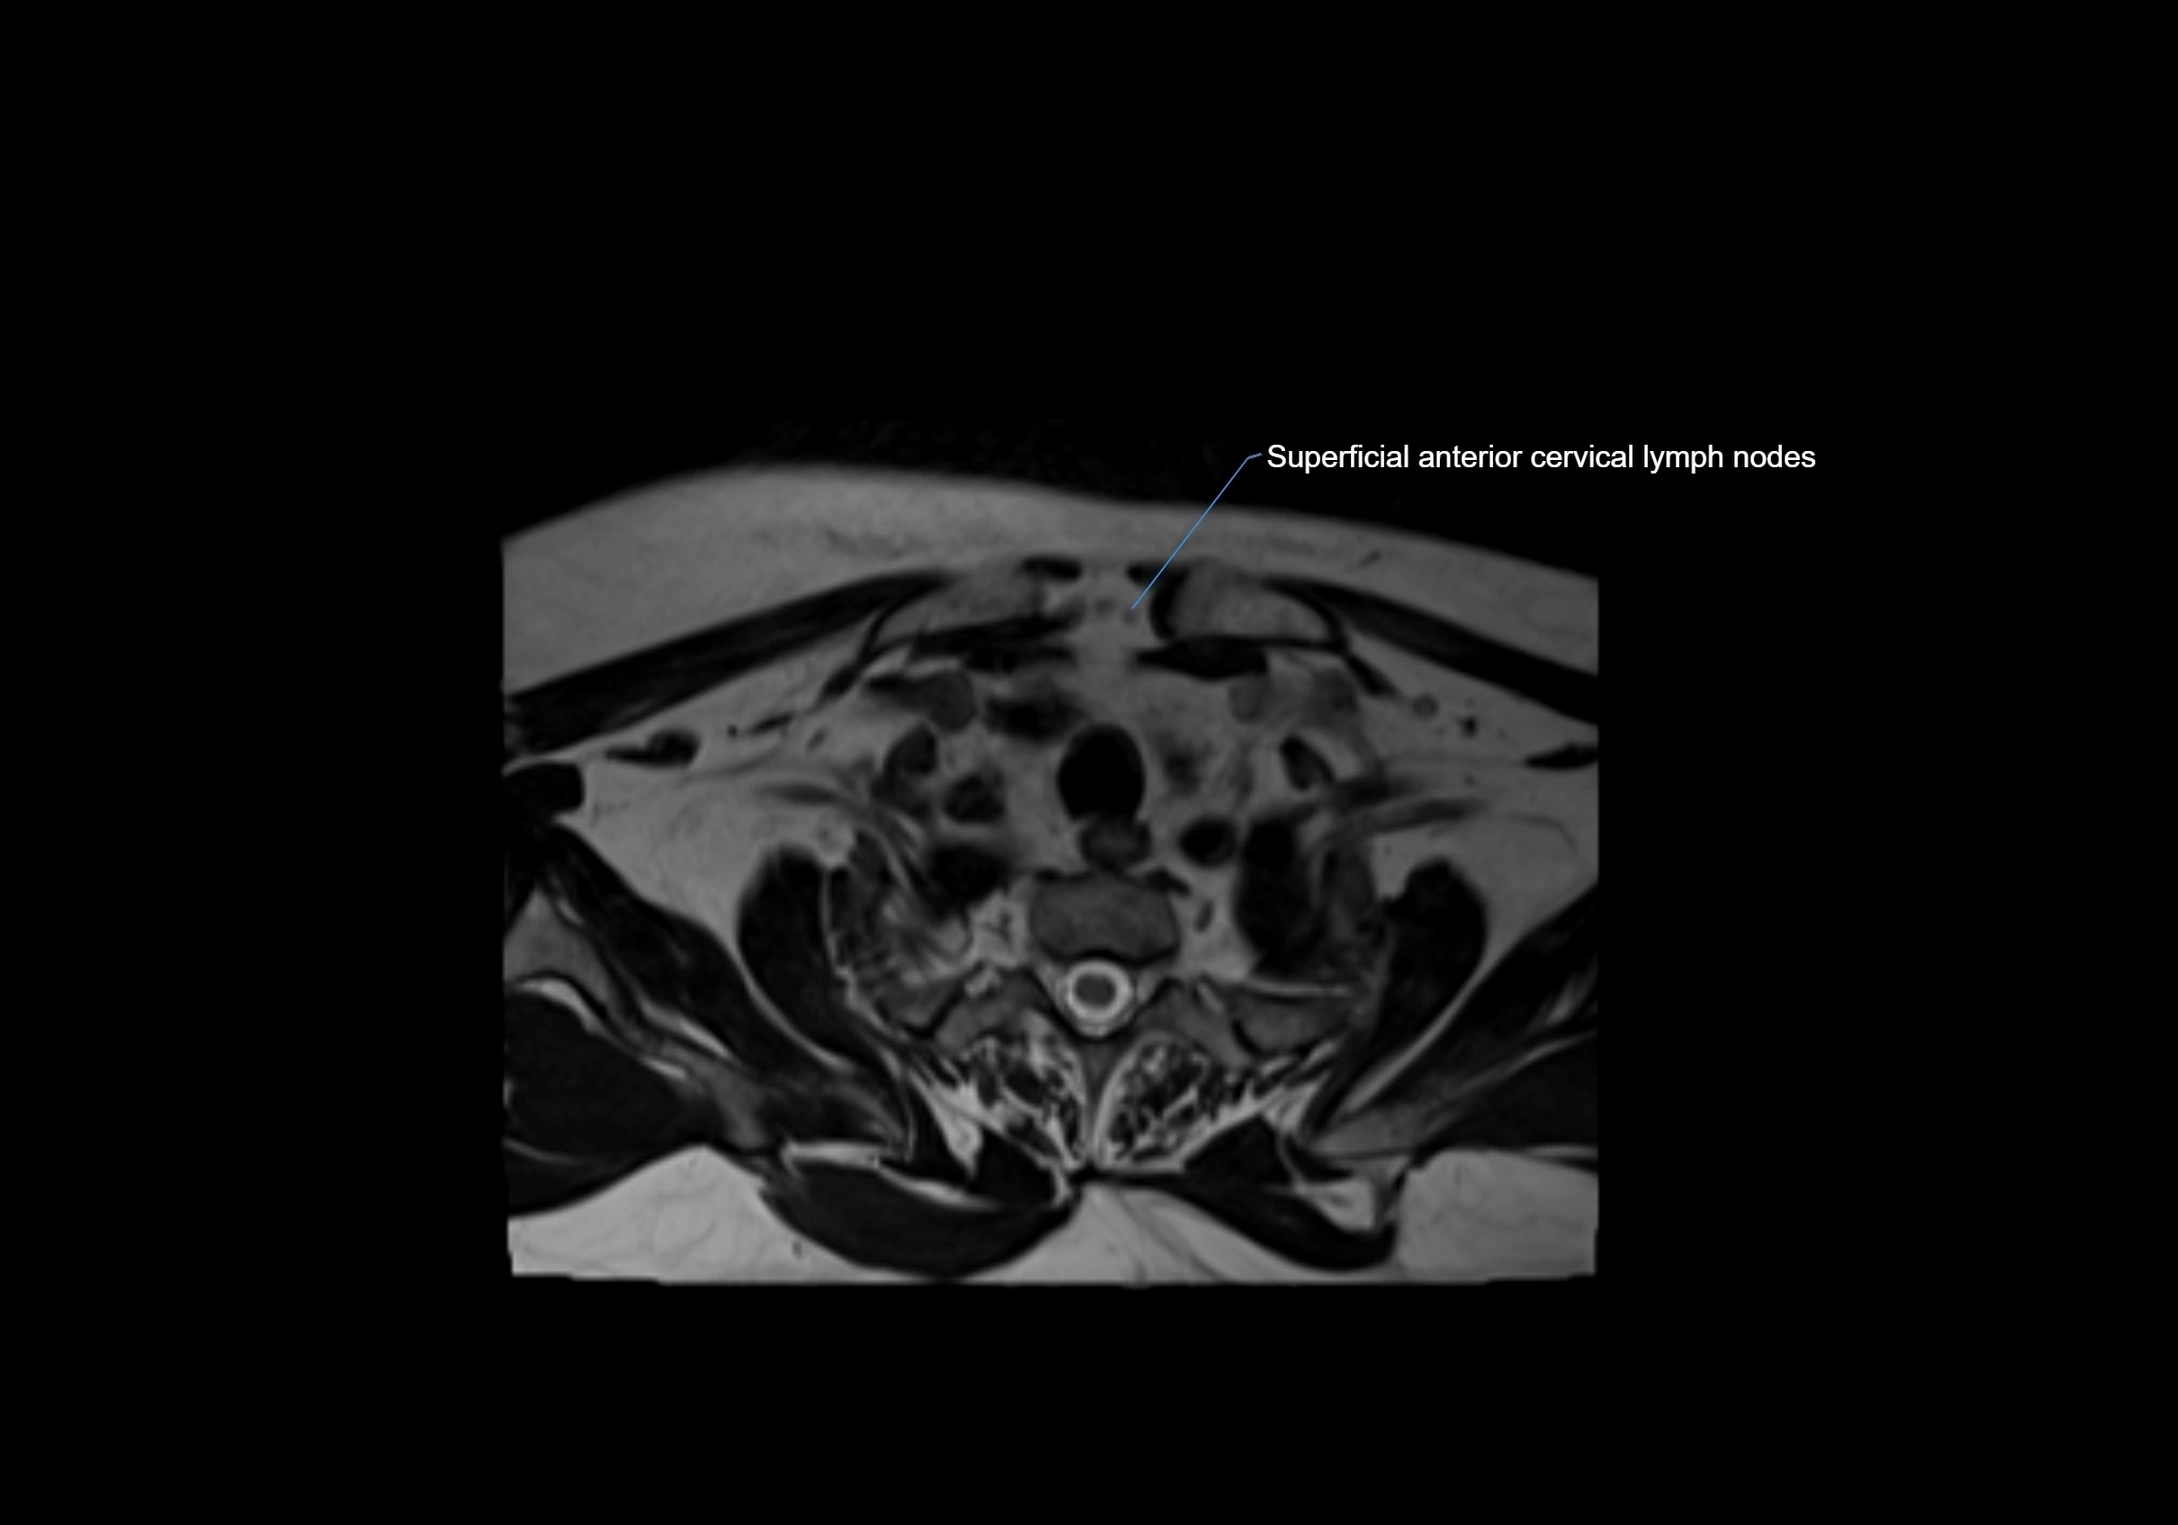

MRI Appearance

T1-weighted images:

• Normal accessory nodes appear as small, oval hypointense to intermediate signal structures within subcutaneous fat

• Surrounded by hyperintense fat, enhancing contrast for visualization

• Pathological nodes may appear enlarged or rounded, sometimes with cortical thickening

T2-weighted images:

• Nodes show intermediate signal, with surrounding fat bright

• Useful for detecting edema, inflammation, or infiltration

• Fatty hilum may appear slightly hyperintense relative to cortex